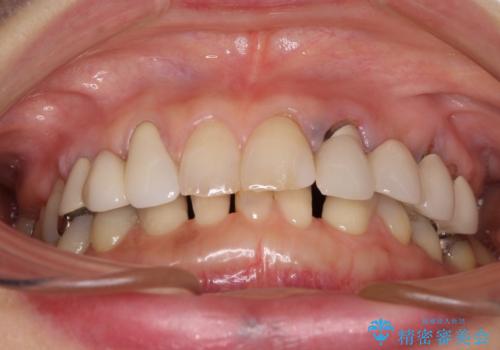

- 割れていると言われて放置してしまった歯や、前歯のデコボコなどが気になるとのことで来院された患者様です。

左上の歯は割れてしまっており、抜歯のうえインプラント治療が必要であり、他にも抜歯の必要な歯がある状態でした。

上顎はほぼ全ての歯をセラミッククラウンにて補綴治療を行う必要があるため、気になるデコボコや深い咬み合わせを改善するために下顎と上顎の臼歯部の矯正治療を行うこととしました。

過蓋咬合(下顎前歯が隠れてしまうほどの深い咬み合わせ)のため、スムーズに歯が動かず矯正治療に時間がかかりましたが、無事に仕上げることができました。